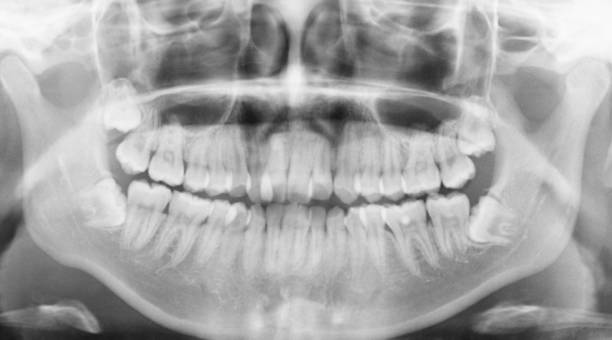

医生先从正侧面看了我的面型,然后用小镜子扒拉开我的嘴巴仔细检查后,就去拍放射片啦。一张全景,另外一张头颅侧位片,可以看到牙齿里面的情况,以及颌骨的情况。

正畸前的全景照

▼

图片来源:作者提供